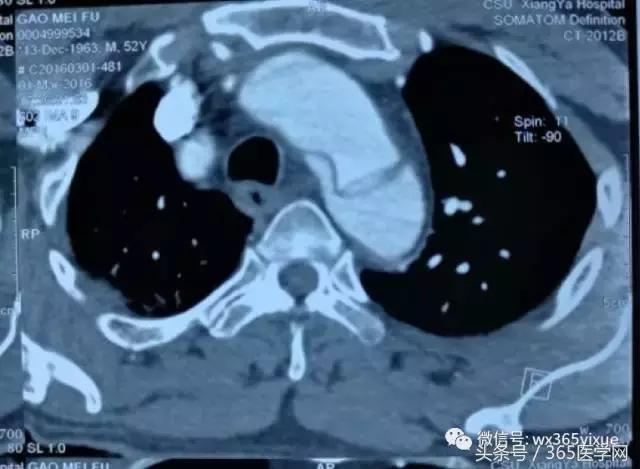

在临床上我们经常碰到主动脉Ⅲ型弓(图1C),即弓部成角陡峭,容易使主动脉支架外鞘在跨弓时打折,从而使支架释放时阻力增大,严重的甚至导致释放支架时移位,造成想象不到的严重后果。这样的情况就对支架材料提出了很高的要求。我们在临床实践中发现,上海微创公司的Hercules Low Profile 直管型覆膜支架系统(图5A)比较适合主动脉弓部成角陡峭的病人。原因有三:其一,它有着目前国内最小的输送系统外径,最小能够达到18F(直径20-36mm支架);其二,它有着覆膜套管跨弓设计,整个输送系统跨弓时阻力小,柔软不易打折,并且在支架释放瞬间稳定不易移位;其三,主动脉夹层是由于动脉壁出现破口,血流冲入导致形成真腔和假腔,由于假腔的压迫真腔一般会相对缩小,形成上粗下细的锥度。传统的胸主动脉支架系统如有些品牌支架没有锥度,头到尾直径没有变化,容易在释放时对相对缩小的真腔管壁造成应力拉扯,留下再发破口的隐患,因此经常需要在后段加入限制性裸支架人为形成锥度,不仅效果得不到很好保证,而且增加了患者经济负担。Hercules Low Profile独有大锥度支架规格,支架锥度范围2-10mm,锥度变化平缓,在释放 后能够更贴壁并且不造成过多拉扯,更适合主动脉夹层患者。对于下面的病例(图5B、C),患者主动脉角度陡峭,破口位置高,就需要选择本身比较柔软、容易过弓的支架,使用微创的公司Hercules Low Profile就能达到很好的效果。

图5A HerculesTM Low Profile 直管型覆膜支架系统

图5B 主动脉弓角度陡峭

图5C 主动脉夹层破口位置高